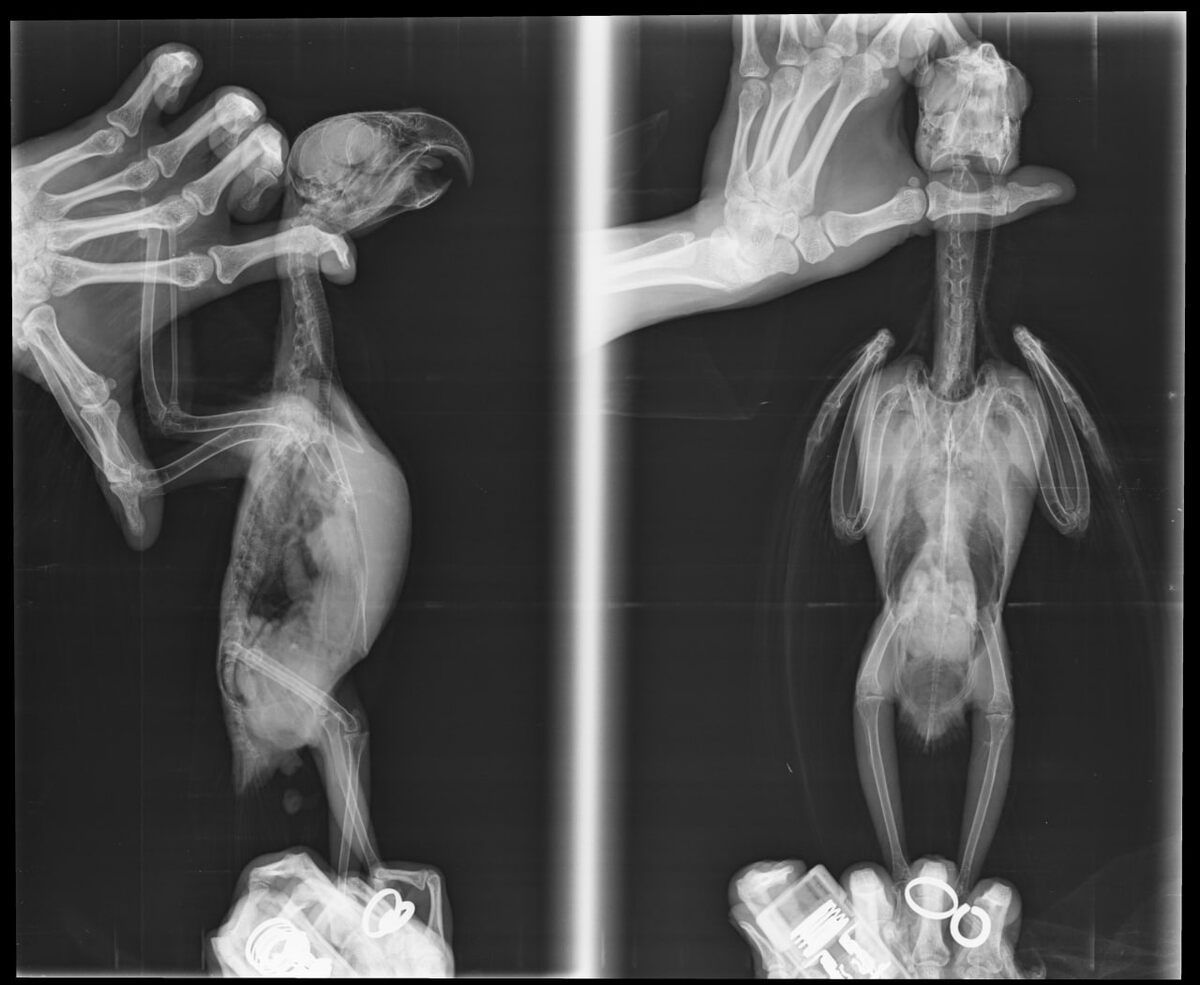

Амазон венесуэльский, пол не опред., >5-6 лет, первичный прием

Рентген: двусторонняя хроническая разлитая пневмония, аэросаккулит правого подключичного отростка межключичного воздухоносного мешка, переднегрудных воздухоносных мешков (наиболее выражен в правом), уплотнение почек с подозрением на склеротизацию.